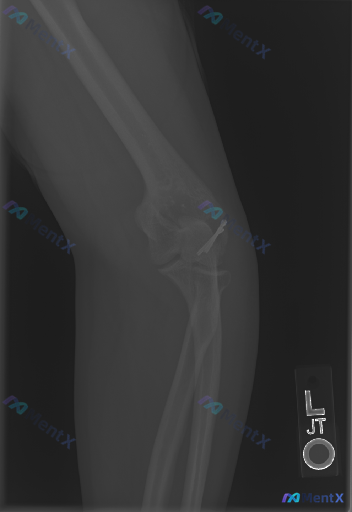

整理到一份左肘关节术后的复查影像资料,X光报告已经出了,但关于这份影像的“异常”解读可能存在不同角度。 核心信息先放出来: - 基础情况:左肘关节侧位片,标记L - 明确发现:肱骨小头/外髁区域有金属内固定物(高密度影,考虑克氏针或微型螺钉) - 骨骼整体:对位良好,关节关系正常,未见新的骨折线 -...